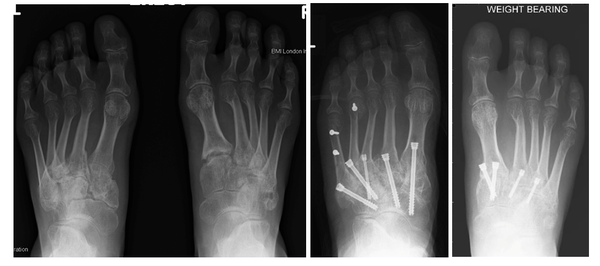

Lisfranc injury with the tearing of ligaments, fracturing of the metatarsal bases and loss of alignment.

The X-ray above shows loss of alignment across the midfoot joints, irregular joint surfaces as a result of multiple fractures.

The X-ray to the left demonstrates well aligned midfoot joints with no signs of arthritis

A car crash has resulted in extensive fractures and poor alignment of the midfoot, with the left side worse than the right. The left foot has subsequently undergone a fusion of all the midfoot articulations (eight joints), whereas the injury on the right was less extensive and just three joints were fused, with less stiffness and better function as a result.